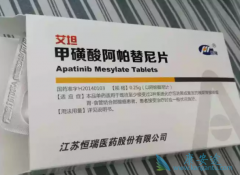

在我国,食管鳞状细胞癌(ESCC)是一种常见的恶性肿瘤,对于一线治疗失败的患者,目前尚标准治疗方案。以往研究表明, 抗肿瘤药品 阿帕替尼或可改善ESCC患者的生存时间。那阿帕替尼联合S-1治疗晚期食管鳞状细胞癌的疗效和安全性如何呢?研究纳入15例一线 ...